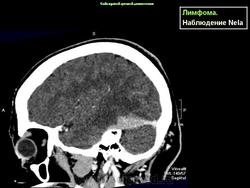

Лимфома.

Лимфома задней черепной ямки